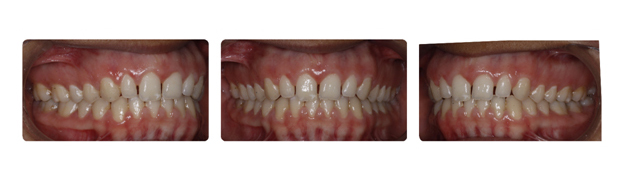

| پس از گذشت دو سال از درمان فک و دندانها مرتب شده و سر جای خود قرار گرفته اند: |

![]() |

| همچنین پس از گذشت یک سال از پایان درمان همچنان نتیجه رضایت بخش است: |